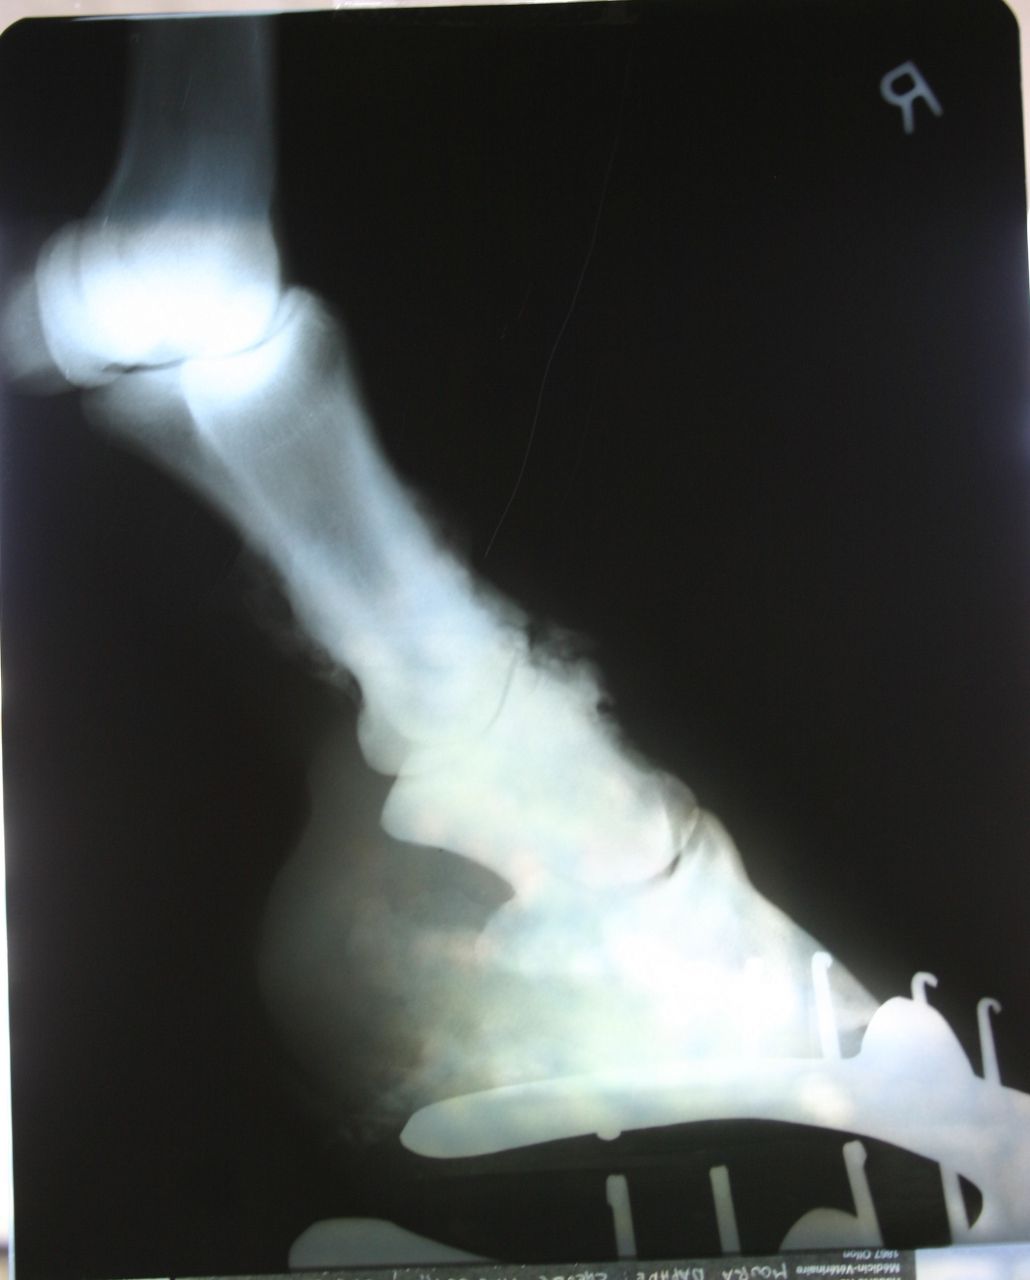

| Dire merci | pour le moment bien, mais ça fait pas longtemps qu'il est sous equipalazone en continu! et puis il avait un autre AI avant, qui était sous forme de pâte, mais j'arrive plus à me rappeler le nom, il me semble que ça finissait par "ure" j'ai fait des photos des dernières radios,s'il y en a que ça intéresse ![]() d'abord l'antérieur droit, le plus touché : on voit bien les formes aux paturons et l'articulation qui est presque entièrement soudée ![]() ![]() ![]() et puis le gauche, un peu moins grave mais bien touché quand même! ![]() ![]() |